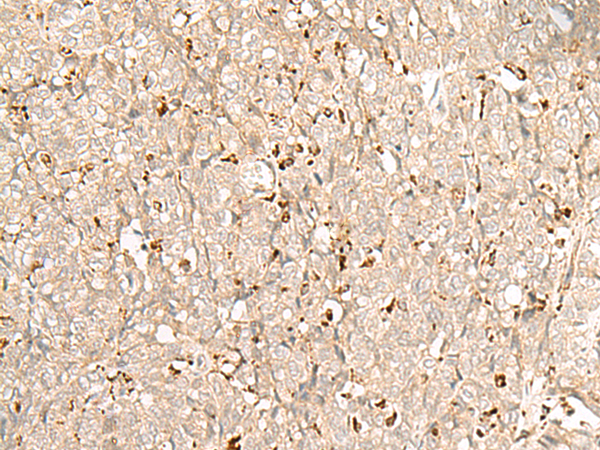

分类: 科研抗体货号: P06583别名: GP210; POM210应用: IHC反应种属: Human, Mouse, Rat